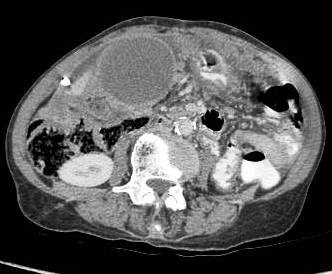

Association with cholelithiasis

Etiology of gallbladder cancer remains obscure although cholelithiasis (Figure 4,5) [3-5], cholecystitis [12], racial and ethnic factors, blood groups, carcinogens, lipid peroxidation products, benign tumors, and secondary bile acids have been implicated as possible causes [13-15].

Figure 5: Gallbladder mass associated with large hyperdense calculus. Gross omental deposits and ascites can be seen. Inferiorly on right side the colon is invaded.